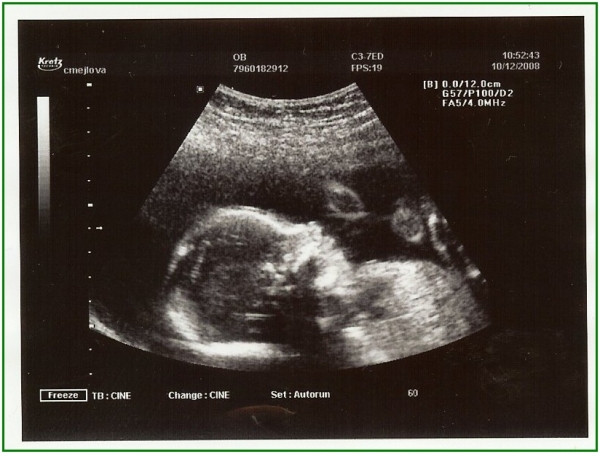

Pod pokličkou poprvé

Pod pokličkou podruhé

Pod pokličkou potřetí